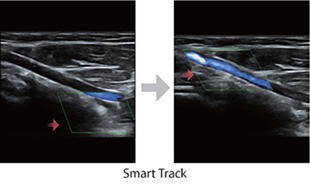

Smart Track

Smart Track menyediakan optimasi yang cepat dan cerdas untuk pencitraan vaskular dengan operasi satu sentuhan yang sederhana. Alat ini bisa mengoptimalkan spektrum Warna, Daya, dan PW dengan melakukan pelacakan mandiri dan mengurangi langkah-langkah yang menghabiskan waktu. Oleh karena itu, alur kerja pemeriksaan vaskular disederhanakan dengan tampilan yang optimal.